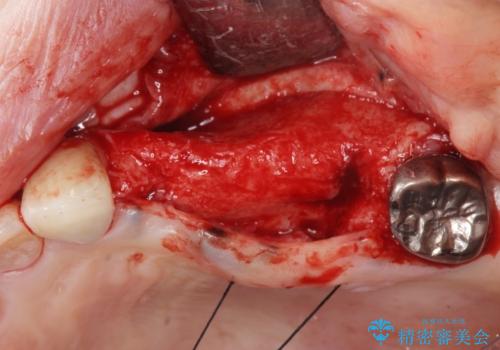

インプラント2本で3本分の咬合機能を回復することができました。(インプラントブリッジ治療)

- 外科手術のため、術後に痛みや腫れ、違和感を伴います